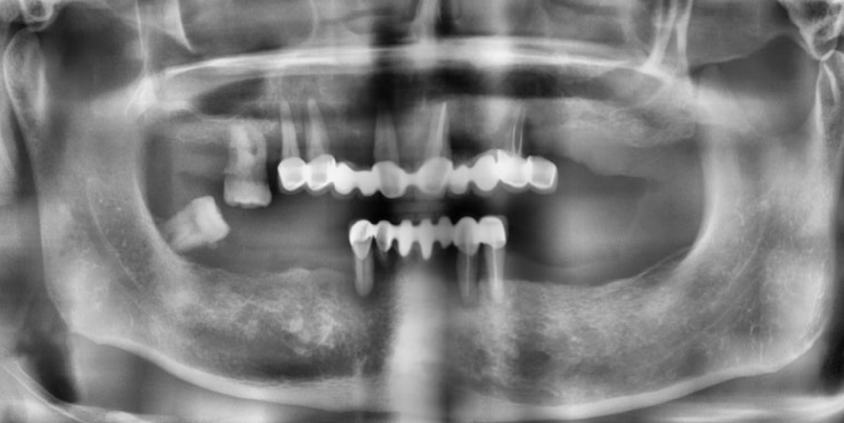

나이가 들면서 전체 치아가 흔들리거나 손상되어 발치 후 전체 임플란트(전악 임플란트)가 필요한 경우가 많아요. 특히 만 65세 이상 환자분들은 평생 1인당 2개까지 임플란트 건강보험 혜택이 적용되니 꼭 확인해 보세요! 이번 증례는 심각한 잇몸 질환으로 모든 치아를 상실한 60대 환자분께서 정교한 맞춤형 전악 임플란트를 통해 건 강한 미소와 저작 기능을 회복한 과정입니다. CASE. 60대 남성 환자, '전체 치아 흔들림'으로 내원 "전체 치아가 흔들리고 아파서 임플란트를 하고 싶어요." 여러 치과를 알아보시던 중, 지인의 소개로 저희 병원을 찾아주셨습니다. 처음부터 전악 임플란트를 염두에 두고, 풍부한 임상 경험을 가진 의료진을 찾고 계셨습니다. 정밀 진단 결과 구강 검진 및 CT 촬영 결과, 환자분의 상태는 매우 심각했습니다. * 구강 상태: 위아래 모든 치아가 심하게 흔들리고, 치아 뿌리가 노출될 정도로 잇몸 조직이 붕괴된 상태였습니다. * CT 및 파노라마 소견: 치아를 지지해야 할 잇몸뼈(치조골)가 염증으로 인해 대부분 소실되어, 치아들이 뼈 속에서 떠 있는 '부유치(floating tooth)' 상태였습니다. 자연치아를 최대한 보존하는 것이 원칙이지만, 이미 치아 뿌리 끝까지 염증이 퍼져 회복이 불가능했습니다. 환자분께 상태를 자세히 설명드린 후, 전체 발치 및 전악 임플란트 계획을 수립했습니다. ![]() ![]() 개인별 맞춤 치료 계획 환자분의 구강 구조와 심미성을 고려하여 아래와 같이 맞춤형 치료 계획을 세웠습니다. * 상악 (윗니): 6개의 임플란트 식립 후 '임플란트 지지 부분틀니 (IARPD)' 붕괴된 앞니 잇몸과 입술의 볼륨감을 심미적으로 회복시키기 위해, 어금니는 임플란트 고정성 보철로 단단히 잡아주고 앞니는 틀니의 잇몸 부분(flange)을 이용해 자연스러운 외모를 재현하는 방식입니다. * 하악 (아랫니): 8개의 임플란트 식립 후 전체 ‘고정성 보철' 전체 치아를 임플란트와 보철물로 단단하게 고정하여 본래 치아처럼 편안하게 사용하는 방식입니다. 치료 과정 1. 발치 및 잇몸 회복 모든 치아를 발치한 후, 염증이 완전히 사라지고 잇몸이 안정될 때까지 약 2개월간 기다렸습니다. 이 기간 동안 환자분의 식사와 심미성을 위해 임시 틀니를 제작해 드렸습니다. ![]() 2. 정확하고 안전한 임플란트 식립 - 상악수술: 잇몸뼈가 얇아 고난도 수술인 상악동 거상술을 동반하여, 계획된 위치에 정확하게 6개의 임플란트를 식립했습니다. 충분한 마취와 정교한 수술, 그리고 숙련된 봉합으로 환자분의 불편감을 최소화하고 빠른 회복을 유도했습니다. ![]() - 하악수술: 최종 보철물의 형태와 기능을 고려하여 적절한 간격과 위치에 8개의 임플란트를 완벽하게 식립했습니다. ![]() 3. 뼈 유착 및 2차 수술 임플란트가 뼈와 단단히 붙는 약 3~4개월 동안 임시 틀니를 사용하며 기다립니다. 이후 모든 임플란트의 ISQ 수치(임플란트 안정성 지수)가 양호한 것을 확인하고, 잇몸 밖으로 임플란트를 노출시키는 간단한 2차 수술을 진행했습니다. ![]() 4. 임시 보철 및 최종 보철 준비 현재는 최종 보철물을 올리기 전, 임시 보철물(PMMA)을 사용하여 환자분이 적응하는 단계를 거치고 있습니다. 임플란트가 완벽하게 식립되었기 때문에 성공적인 최종 결과가 기대됩니다. 전악 임플란트는 단순한 치아 보철을 넘어, 무너진 식생활과 자신감을 회복하는 중요한 치료입니다. 이백점치과는 최소한의 임플란트 식립으로 통증과 불편을 줄이면서도 안정적이고 심미적인 결과를 추구합니다. 풍부한 임상 경험과 높은 환자 만족도로 증명된 실력으로, 치아가 전혀 없는 분들도 다시 편안한 식사와 활짝 웃는삶을 되찾을 수 있습니다. 당신의 현명한 선택, 이백점치과와 함께하세요. |